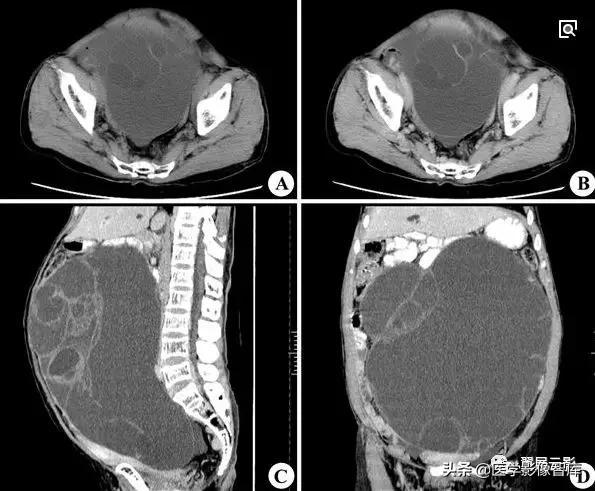

卵巢囊腺瘤

本病分为浆液性囊腺瘤和黏液性囊腺瘤,约占卵巢原发肿瘤的1/4,双侧发生率约为15%,浆液性囊腺瘤和黏液性囊腺瘤可以并存,浆液性囊腺瘤呈单房或多房改变,黏液性囊腺瘤多为多房改变,好发年龄为20—50岁,临床症状有腹部不适或隐痛,腹部包块等,少数伴有月经紊乱,浆液性囊腺瘤患者有时可出现腹水,病理表现:肿瘤切面为单房或多房性,囊壁光滑或有乳头状突起,浆液性囊腺瘤囊壁上皮为单层立方或矮柱状上皮;黏液性囊腺瘤囊壁上皮为单层黏液柱状上皮。

注意观察描述卵巢囊腺瘤的大小及均匀液性长T1,长T2信号特点,同时应观察描述囊腺瘤的分隔和乳头状壁结节,一般在T2WI上显示清晰,黏液性囊腺瘤内有粘蛋白,T1WI呈等或略高信号,T2WI为高信号,此点可与浆液性囊腺瘤相鉴别。

卵巢癌

在女性生殖系统恶性肿瘤中,卵巢癌的发病率仅次于宫颈癌,多数患者早期无症状或症状轻微,就诊时往往已有盆腔广泛转移,卵巢癌来源于上皮,其组织类型多样,其中浆液性囊腺癌所占比例较大,约占42%。肿瘤播散主要通过肿瘤表面细胞种植和淋巴转移,血行播散少见。

注意观察和描述肿瘤的性质,囊实性肿块一般为囊腺癌,其边界较清楚,囊壁及分隔厚薄不均,壁结节可融合成块,同时应描述肿瘤的大小范围,左右侧起源,是否有盆腔器官受侵,出现腹水时应注意其T1WI,T2WI信号较一般体液高,为转移性血性腹水。